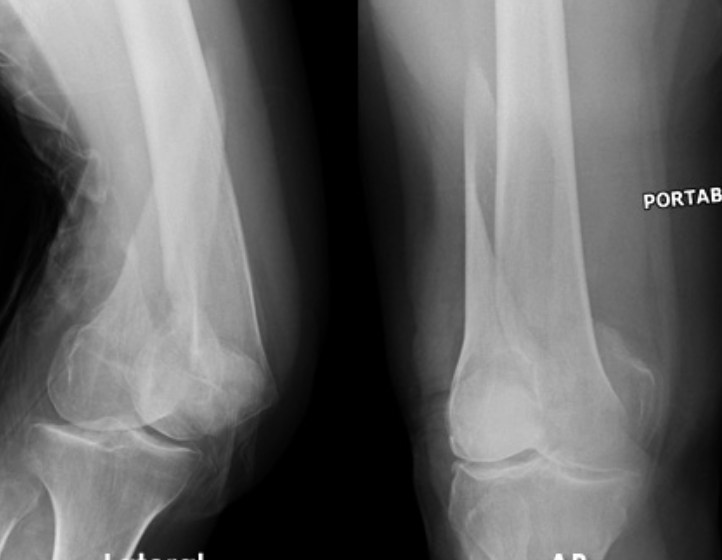

Maisonneuve injury